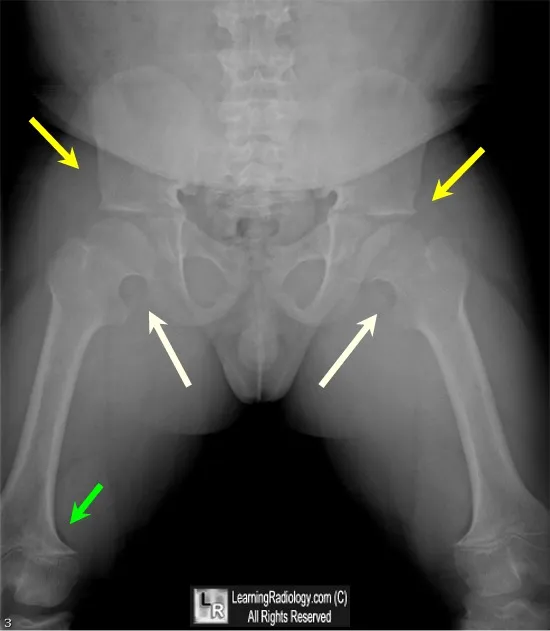

- Radiology:

- Spine: Caudal narrowing of interpedicular distance.

- Pelvis: "Champagne-glass" pelvic inlet.